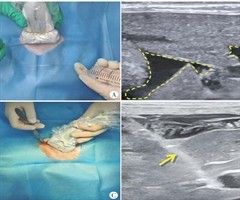

超声引导下人工腹水辅助兔肝出血模型建立的实验研究

摘要目的探讨超声引导下注射人工腹水辅助兔肝活动性出血模型建立的应用价值。方法将20只成年雄性家兔分为人工腹水辅助组(A组)和直接穿刺组(B组),每组各10只,其中A组于超声引导下注射人工腹水,经皮穿刺切割肝脏建立兔肝活动性出血模型;B组于超...